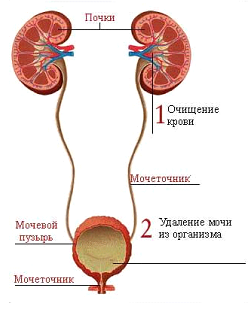

Мочевой пузырь выполняет важнейшую функцию. Являясь частью системы мочеотделения, он собирает

мочу, поступающую из почек через мочеточники, накапливает эту жидкость и выводит ее из организма посредством процесса мочеиспускания. Этот орган расположен в малом тазу: прикреплен к лобковым костям.